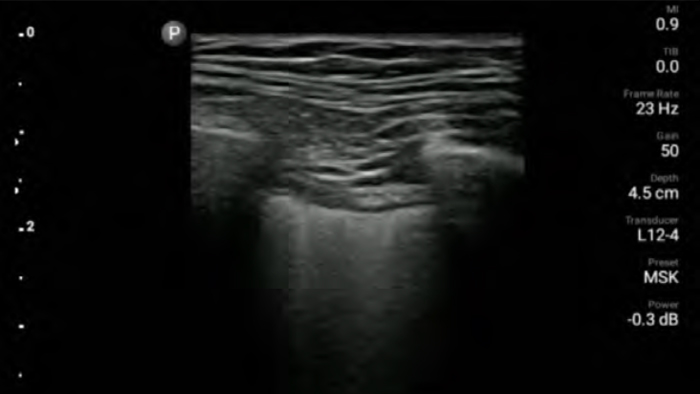

Improve precise placement on visually defined nerve blocks, so you can get in and out faster. And perform quick and thorough post-operative follow ups.

in needle guided procedures

Lumify handheld ultrasound for anesthesiology helps you clearly visualize border definition with your needle placement, surrounding nerves, vessels and fascial planes.

Lumify helps you clearly visualize needle placement, surrounding nerves, vessels and fascial planes.

Broadband linear array transducer

Lumify L12-4 broadband linear array transducer

• 12 to 4 MHz extended operating frequency range

• Aperture size: 34mm

• 2D, steerable color Doppler, M-mode, advancedXRES and multivariate harmonic imaging, SonoCT

• High resolution imaging for shallow applications: soft tissue, vascular, superficial, musculoskeletal and lung

• Center line marker

• USB-C transducer with replaceable cable